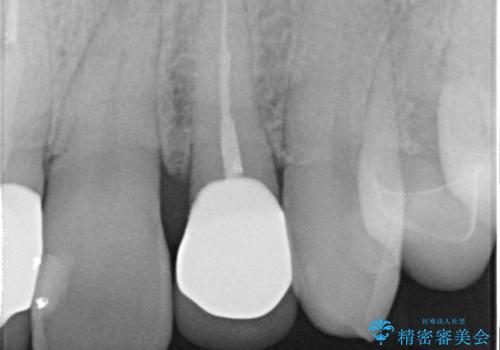

継ぎ目のないクラウンで修復処置していきます。

- 左上2 仮歯+ジルコニアクラウン:11,000円+121,000円費用は治療当時の料金となります

精度の良い被せ物を装着することで、違和感のない自然な見た目を獲得することができます。